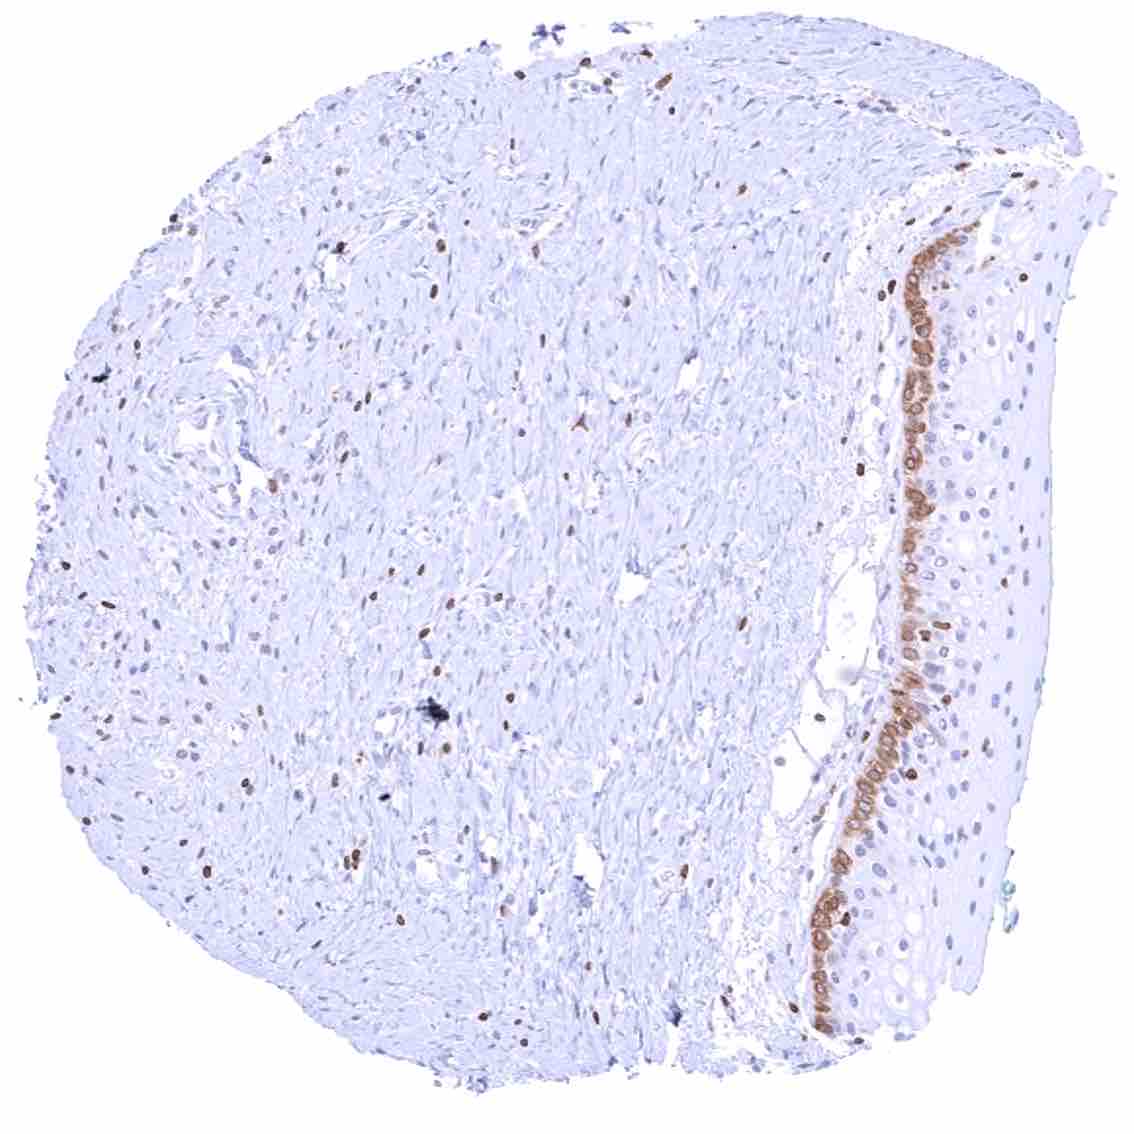

Uterus, ectocervix – Strong cytoplasmic bcl-2 staining of basal cells of the squamous epithelium in this sample.

Uterus, ectocervix – Weak cytoplasmic bcl-2 staining of basal cells of the squamous epithelium.